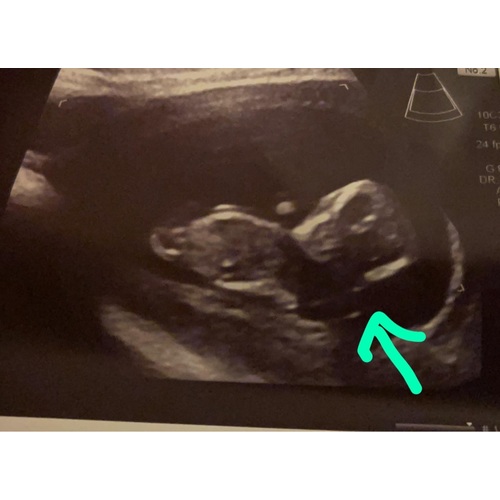

Ik had gisteren een 20 weken echo en toen gingen ze het vocht ook meten in haar hoofd. Die plek was bij mij 6.9 mm. Als die 10 mm zou zijn, dan zou het een waterhoofd zijn. Mijn kind is verder gezond. Heb ook de nipt test gedaan en de 20 weken echo was verder ook goed.

Hoi, wij waren afgelopen maandag in Maastricht umc. Geen vocht in hoofdje maar in nek van 4.4mm. Ik heb vlokkentest afgewezen en moet over 4 weken terug komen voor vruchtwaterpunctie. Volgens de specialist zaten we bij de 70% dat het gewoon een gezond kindje was omdat de meting niet helemaal duidelijk was omdat de baby te veel bewoog. De 4.4mm kon ook minder zijn. S we boven de 5,5 zaten was het ernstig maar voor nu geen zorgen zei hij. Maar dan nog maak je je zorgen omdat je gewoon geen zekerheid hebt. Maar de vruchtwaterpunctie moet het uitwijzen....

Hebben ze toevallig bij u gezegd hoe groot de plek is?